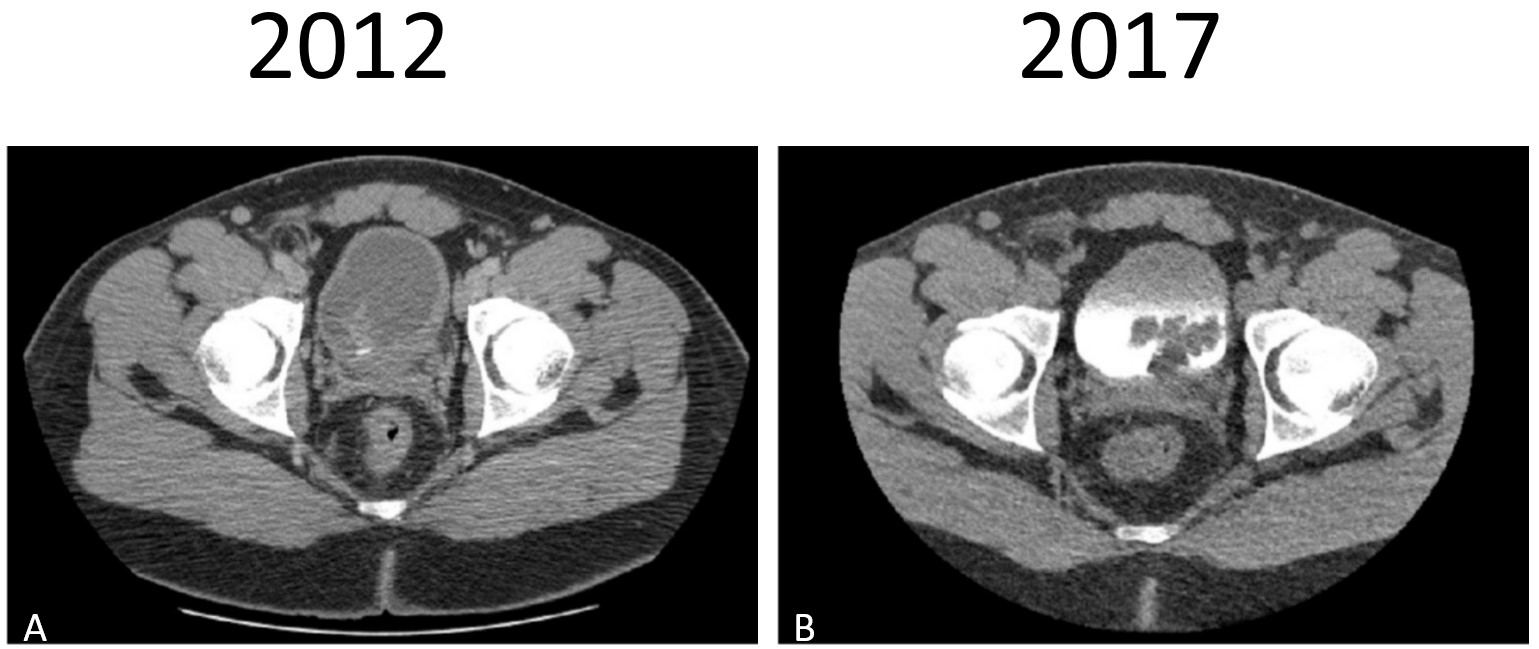

A 35-year-old African American male with history of recurrent urinary tract infections, lower urinary tract symptoms, and a benign urinary bladder fibroepithelial polyp (FEP) (status post transurethral resection 5 years prior with no follow-up cystoscopy), presented with intermittent flank pain and new onset hematuria. He reported longstanding urinary frequency, incomplete emptying, and nocturia. He had no relevant family history and social history was significant for tobacco smoking. Physical examination demonstrated moderate left flank tenderness with unremarkable vital signs. Urinalysis showed mild hematuria and proteinuria with negative urine culture. Abdominal/pelvic CT with contrast displayed an irregular 5x4cm filling defect in the bladder, similar in location to the benign FEP discovered previously (Fig. 1). Cystoscopy revealed a lobulated, polypoid lesion seemingly attached to the left bladder neck (Fig. 2). Transurethral resection of the mass was attempted but incompletely achieved due to anteriorly positioned mass. In addition to the left bladder neck, mass was contiguous with the left intraurethral prostatic lobe. Histologic examination of the entirely submitted specimen demonstrated a biphasic epithelial-stromal tumor with benign urothelial lining and malignant stromal cells displaying marked cytologic atypia, numerous mitoses, and necrosis. There was also morphologic and immunophenotypic evidence of rhabdomyoblastic differentiation (e.g. myogenin, myo-D1, and desmin positive), sharply contrasting the findings of the previously resected lesion at this site (Fig. 3). Although both lesions had a biphasic polypoid appearance with benign urothelial lining, the stromal component of the current lesion was frankly malignant and consistent with the diagnosis of a Grade 3 (FNCLCC grading) rhabdomyosarcoma (Fig. 4). There was no evidence of sarcomatoid carcinoma and no PAX3/FOXO1 or PAX7/FOXO1 fusion transcript was detected by RT-DNA amplification.

Figure 1: Computed tomography (CT) imaging. A) Fibroepithelial polyp (2012): Abdominal/pelvic CT with contrast demonstrating bladder wall thickening/mass lesion. B) Rhabdomyosarcoma (2017): Abdominal/pelvic CT with contrast demonstrating a 5x4cm filling defect in bladder.